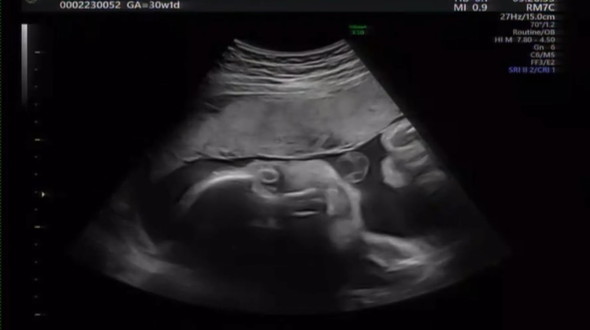

「えっと、、これよりホラーなエコーありますか、、。」

画像提供:KITO(@ki_to1018)さん